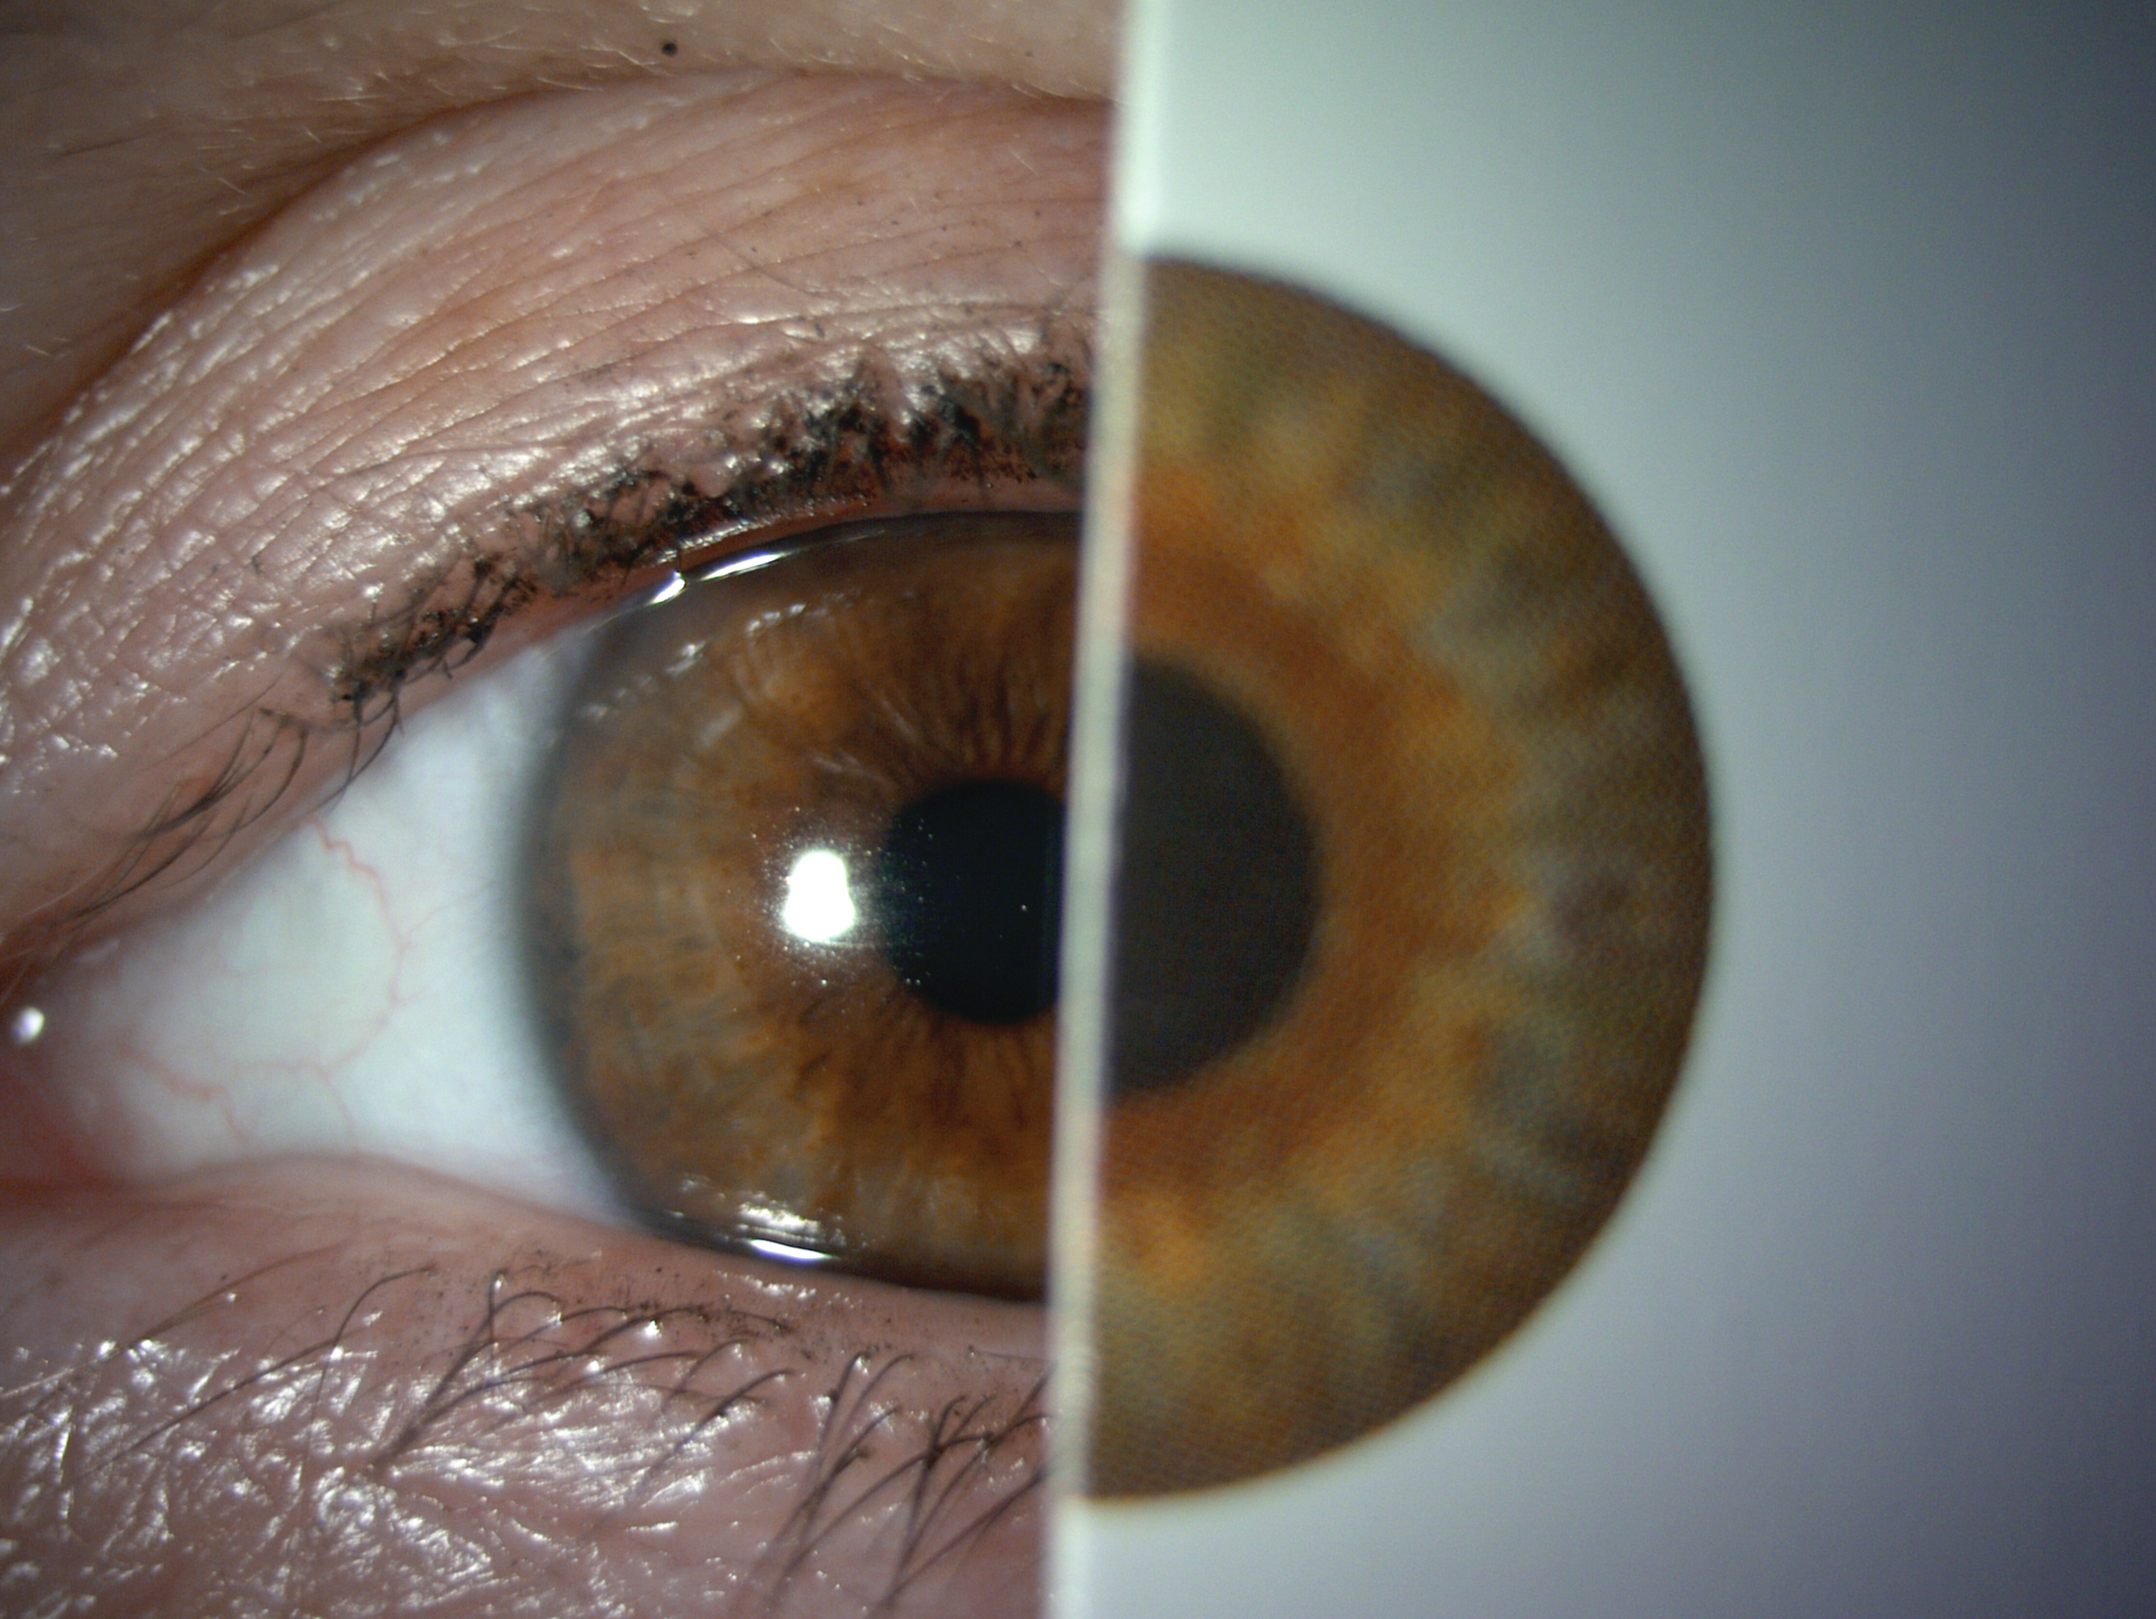

Scleral lenses are large diameter gas-permeable contact lens devices.

Rather than sitting directly on the eye like a traditional soft lens, scleral lenses only touch the sclera (the white part of the eye) and vault entirely over the cornea (the front of your eye - a clear layer of tissue that covers your iris, pupil and lens). This vault - the space between the contact lens and your cornea - is filled with fluid and creates a new, perfect focusing surface.

By vaulting over the eye with fluid, we are able to manage complicated eye conditions such as astigmatism, keratoconus, corneal transplants, severe dry eye, corneal scarring, LASIK complications and more. These lenses can be life changing.

When customizations are needed or when conventionals fall short. Includes scan-based, freeform, and EyeFitPro (impression molding). 40,000 data points are collected to create a custom fit lens.

For the ultimate precise fit and full customization options utilizing impression molding (EyePrintPro). 80,000 points of data are collected to create a truly unique scleral lens.